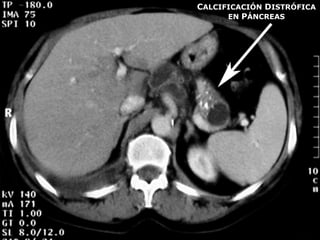

 La calcificación distrófica es muy frecuente.

CALCIFICACIÓN DISTRÓFICA

EN PÁNCREAS